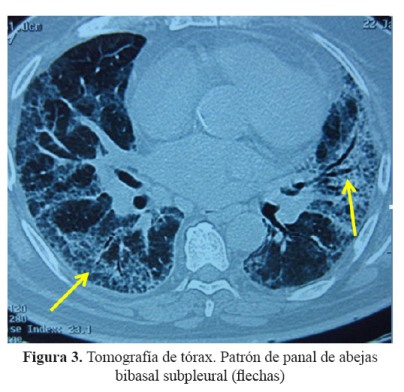

Se realizó una tomografía de tórax que mostró infiltrados intersticiales bilaterales con patrón en vidrio esmerilado en tercio medio e inferior a predominio del pulmón izquierdo (Figura 2), mientras que en las bases se observó patrón en panal de abeja con engrosamiento de los septos y bronquiectasias de tracción ( Figura 3).

El paciente tenía antecedente de insuficiencia cardíaca y de fibrilación auricular paroxística por lo que recibía tratamiento con amiodarona, acudió con una historia de 3 semanas de tos, disnea y fiebre, llamando la atención desde el ingreso la radiografía de tórax con infiltrado bibasal tipo consolidado pero también con compromiso intersticial en la periferia. Recibió tratamiento para neumonía adquirida en la comunidad con ceftriaxona y claritromicina, además diuréticos por el antecedente de insuficiencia cardíaca. La evolución fue estacionaria, se cambió la cobertura antibiótica a ceftazidima y amikacina; sin embargo, la fiebre persistió. La tomografía de tórax confirmó lo que se evidenciaba en la radiografía, un compromiso intersticial difuso, con áreas de patrón en vidrio esmerilado en la periferie y patrón en panal de abeja en bases.